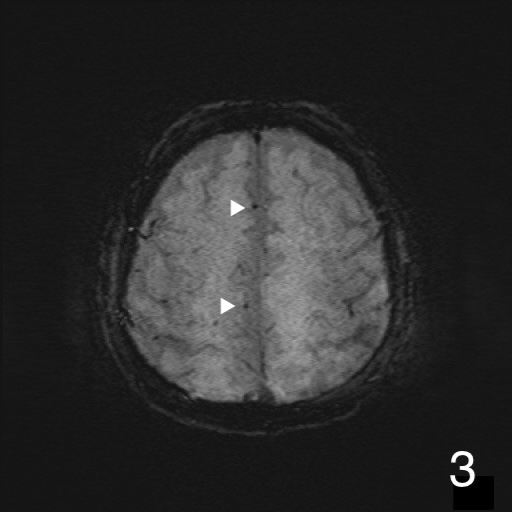

Abstract Image